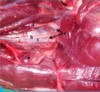

ligation of the Maxillary v.